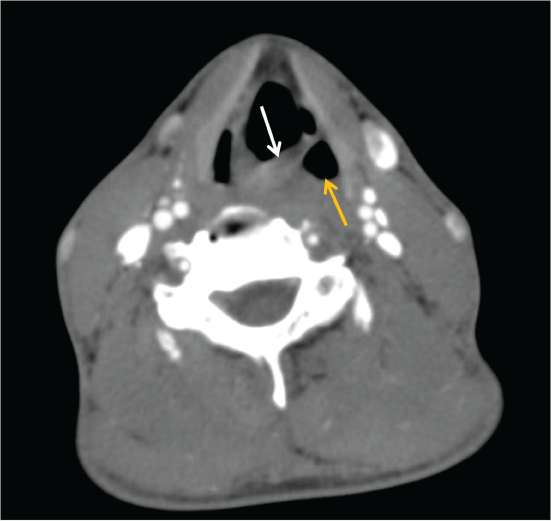

A 37-year-old non-smoker male patient with a 6-month history of hoarseness admitted to our hospital. Laryngoscopic examination revealed left vocal cord paralysis with immobile vocal cord in paramedian position. The patient underwent neck and chest CT imaging. Neck CT demonstrated thickening and medial deviation of the left vocal cord, dilatation of the left piriform sinüs suggesting left vocal cord palsy (Figure 1). Chest CT showed a fusiform aneurysmal dilatation of the proximal left pulmonary artery with 51 mm diameter (Figure 2). Left laryngeal nerve had been compressed between pulmonary artery aneurysm and arcus aorta.

Figure 1: Neck CT image demonstrates thickening and medial deviation of the left vocal cord (white arrow) and dilatation of the left piriform sinus (yellow arrow) suggesting left vocal cord palsy.